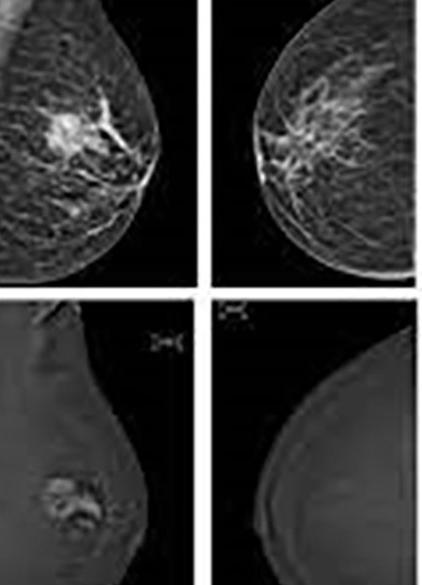

Η μαστογραφία είναι το μαζικότερο και φθηνότερο μέσο απεικόνισης του μαστού. Η μαστογραφία είναι μια ακτινογραφία που χρησιμοποιεί τα χαρακτηριστικά διαφορικής εξασθένησης του ιστού για την αξιολόγηση του καρκίνου του μαστού.

Είναι ένα σύστημα απεικόνισης, το οποίο χρησιμοποιεί ακτίνες Χ χαμηλής δόσης για το μαστό.

Η μαστογραφία με αντίθεση (CEM) είναι χρήσιμη για την επίλυση αμφίβολων ευρημάτων που ανιχνεύονται σε συμβατικές απεικονιστικές εξετάσεις μαστού.